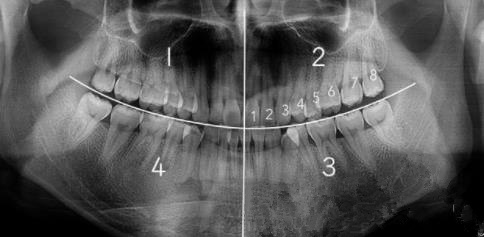

從(cong) 正門牙開始往後數,如果有第8顆牙齒就是立世牙

正常的立事牙多嗎?

不多,可以說極少。

因為(wei) 立世牙可以保留的條件比較嚴(yan) 苛,一般需要滿足這些條件:立世牙萌出位置正、方向對,有相應正常的對頜牙,且和鄰牙(第二磨牙)和周圍組織關(guan) 係都正常,能夠正常行駛牙齒咀嚼功能。

而大部分的立世牙都無法滿足這幾個(ge) 條件。通常出現的是反複發炎、抵到鄰牙甚至造成鄰牙齲壞、容易嵌塞食物、沒有對頜牙等情況的,而這些情況單獨或者多個(ge) 出現都會(hui) 影響口腔健康,所以一般都建議拔除處理。

正常立世牙長什麽(me) 樣子的,不用拔除的立世牙是哪種

一般來說,不用拔除的立世牙,通常如下圖所示,要麽(me) 是極少數出現的堂堂正正有上下牙,而且位置正,可以發揮咀嚼作用;要麽(me) 是上麵的特殊情況,可以牽引出來替代磨牙使用的;再者就是完全埋伏在牙床內(nei) ,不影響鄰牙以及周圍組織,這樣的也可以暫時觀察。